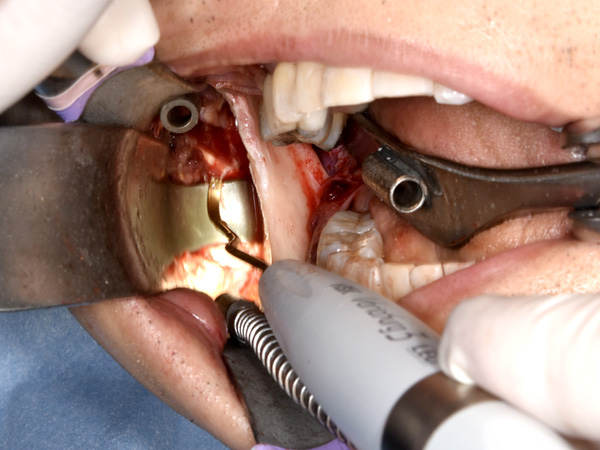

実際の下顎枝垂直骨切り術(IVRO)の様子

IVROの手術のはじまり

右側のかみ合わせを確認しています。

お口の中の状態を確認します。

頬っぺた側、舌側の粘膜を伸展させます。

使用するのこぎりです。

テープの位置は神経にぶつからないようにするためのガイドラインです。

IVROの手術

切開して、骨を露出します。

舌側の神経に気を付けながら、骨を切り始めます。